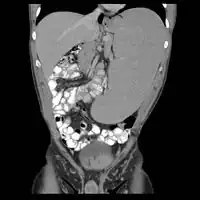

-

Non-Hodgkin lymphoma with hepatic involvement